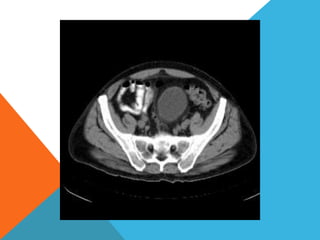

El paciente presentó síntomas de sangrado digestivo y pérdida de peso. Exámenes revelaron gastritis crónica asociada a H. pylori. Un tumor fue descubierto en una colonoscopia normal. La cirugía removió un tumor fibroide solitario, una rara neoplasia mesenquimal que usualmente crece lento y tiene bajo potencial de malignidad. El pronóstico después de la remoción quirúrgica es generalmente bueno.